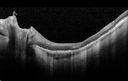

Choroidal Hemangioma - Diffuse - Enhanced Depth Imaging Spectral Domain OCT Line Scan - Normal Eye729 viewsNormal Choroidal Thickness in Right EyeFeb 12, 2014

Choroidal Hemangioma - Diffuse - Enhanced Depth Imaging Spectral Domain OCT Line Scan - Normal Eye620 viewsNormal Choroidal Thickness in Right EyeFeb 12, 2014